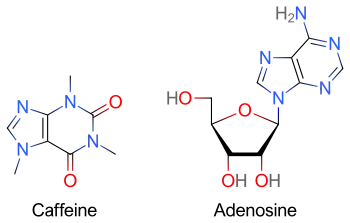

Caffeine is a central nervous system (CNS) stimulant of the methylxanthine class.[13] It is mainly used as a eugeroic (wakefulness promoter) or as a mild cognitive enhancer to increase alertness and attentional performance.[14][15] Caffeine acts by blocking binding of adenosine to the adenosine A1 receptor, which enhances release of the neurotransmitter acetylcholine.[16] Caffeine has a three-dimensional structure similar to that of adenosine, which allows it to bind and block its receptors.[17] Caffeine also increases cyclic AMP levels through nonselective inhibition of phosphodiesterase.[18]

Caffeine is a bitter, white crystalline purine, a methylxanthine alkaloid, and is chemically related to the adenine and guanine bases of deoxyribonucleic acid (DNA) and ribonucleic acid (RNA). It is found in the seeds, fruits, nuts, or leaves of a number of plants native to Africa, East Asia and South America,[19] and helps to protect them against herbivores and from competition by preventing the germination of nearby seeds,[20] as well as encouraging consumption by select animals such as honey bees.[21] The best-known source of caffeine is the coffee bean, the seed of the Coffea plant. People may drink beverages containing caffeine to relieve or prevent drowsiness and to improve cognitive performance. To make these drinks, caffeine is extracted by steeping the plant product in water, a process called infusion. Caffeine-containing drinks, such as coffee, tea, and cola, are consumed globally in high volumes. In 2020, almost 10 million tonnes of coffee beans were consumed globally.[22] Caffeine is the world's most widely consumed psychoactive drug.[23][24] Unlike most other psychoactive substances, caffeine remains largely unregulated and legal in nearly all parts of the world. Caffeine is also an outlier as its use is seen as socially acceptable in most cultures and even encouraged in others.

In the absence of caffeine and when a person is awake and alert, little adenosine is present in CNS neurons. With a continued wakeful state, over time adenosine accumulates in the neuronal synapse, in turn binding to and activating adenosine receptors found on certain CNS neurons; when activated, these receptors produce a cellular response that ultimately increases drowsiness. When caffeine is consumed, it antagonizes adenosine receptors; in other words, caffeine prevents adenosine from activating the receptor by blocking the location on the receptor where adenosine binds to it. As a result, caffeine temporarily prevents or relieves drowsiness, and thus maintains or restores alertness.[9]

Because caffeine is both water- and lipid-soluble, it readily crosses the blood–brain barrier that separates the bloodstream from the interior of the brain. Once in the brain, the principal mode of action is as a nonselective antagonist of adenosine receptors (in other words, an agent that reduces the effects of adenosine). The caffeine molecule is structurally similar to adenosine, and is capable of binding to adenosine receptors on the surface of cells without activating them, thereby acting as a competitive antagonist.[166]